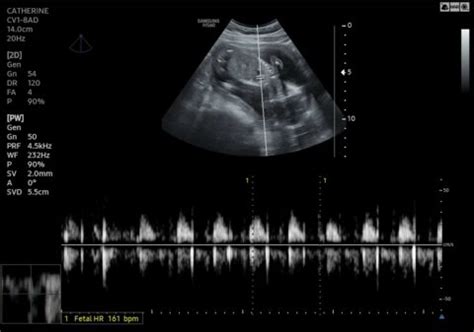

Alright, let’s get to the juicy stuff – the actual fetomaternal announcements from 2023 that have been making waves. One of the biggest areas of progress has been in non-invasive prenatal testing (NIPT). While NIPT isn’t entirely new, 2023 has seen significant improvements in its accuracy and expanded capabilities. We’re talking about detecting a wider range of chromosomal abnormalities with even greater precision, often earlier in the pregnancy. This is huge because it allows for earlier intervention and more informed decision-making for parents. It’s like having a crystal ball, but way more scientific and reliable! Another massive area is the advancement in fetal therapy. This refers to treatments performed on the fetus while still in the womb to correct birth defects. While still a highly specialized field, the techniques and success rates are continually improving. New surgical methods and improved imaging technologies are making previously impossible interventions a reality. Think about correcting congenital heart defects or certain types of spina bifida before birth! The implications for reducing lifelong disabilities are profound. Furthermore, there’s been a considerable focus on maternal mental health during and after pregnancy. Recognizing the significant impact that conditions like prenatal and postpartum depression can have on both the mother and the baby’s development, new screening tools and treatment protocols have been introduced. This holistic approach, considering the mother’s psychological well-being as integral to the fetomaternal unit, is a game-changer. It emphasizes that a healthy pregnancy is not just about physical health but also mental and emotional resilience. The fetomaternal announcements in 2023 also include updates to screening protocols for conditions like gestational diabetes and preeclampsia. These updates often involve refined risk assessment models and potentially earlier or more frequent screening for high-risk individuals. The aim is to catch these conditions sooner, allowing for timely management and preventing severe complications. We’ve also seen strides in understanding the long-term impacts of various pregnancy complications on both mother and child, leading to better follow-up care recommendations. The continuous evolution in diagnostic imaging, such as enhanced ultrasound and MRI techniques, offers unprecedented views of fetal development and potential issues. These technological leaps are directly contributing to more accurate diagnoses and personalized treatment plans within the fetomaternal domain. The collaborative efforts between different medical specialties, including neonatology, cardiology, neurology, and genetics, are also fostering more comprehensive care pathways. This multidisciplinary approach ensures that every aspect of the fetomaternal unit’s health is considered, from conception through to postpartum recovery and beyond.

When we talk about fetomaternal health, accurate diagnostics are the bedrock. In 2023, the advancements in prenatal diagnostics have been nothing short of revolutionary. Gone are the days when prenatal screening was limited and invasive procedures carried significant risks. Today, we have sophisticated tools that offer incredible insights with minimal or no risk to the mother or baby. As mentioned earlier, Non-Invasive Prenatal Testing (NIPT) has seen major upgrades. Originally used to screen for common chromosomal aneuploidies like Down syndrome (Trisomy 21), Edwards syndrome (Trisomy 18), and Patau syndrome (Trisomy 13), newer versions can now detect a broader spectrum of genetic conditions, including microdeletions and certain single-gene disorders. This expanded scope provides parents with a more comprehensive genetic profile of their fetus earlier in pregnancy, allowing for better planning and peace of mind. The technology behind NIPT involves analyzing cell-free fetal DNA (cffDNA) circulating in the mother’s blood. The accuracy and sensitivity of these tests continue to improve, making them a reliable first step for many expectant mothers. Beyond NIPT, diagnostic imaging has also taken a huge leap forward. 3D and 4D ultrasounds are now providing incredibly detailed, almost lifelike images of the fetus , allowing for earlier and more accurate detection of structural abnormalities. Think heart defects, cleft lips, or skeletal issues – these can often be identified with remarkable clarity. Furthermore, advancements in fetal MRI are offering even greater detail, especially for imaging the fetal brain and complex organ systems, complementing ultrasound findings and aiding in diagnosis when ultrasound is inconclusive. The integration of artificial intelligence (AI) into diagnostic imaging is another exciting development. AI algorithms can analyze medical images faster and potentially with greater accuracy than the human eye, assisting radiologists and sonographers in identifying subtle anomalies that might otherwise be missed. This synergy between human expertise and AI is optimizing the diagnostic process in the fetomaternal field. Genetic counseling also plays a pivotal role. With the increased availability of genetic testing, genetic counselors are crucial in helping parents understand the results, their implications, and the available options. Their expertise ensures that the complex information derived from prenatal diagnostics is communicated clearly and compassionately. The continuous refinement of these diagnostic tools means that potential issues can be identified and addressed much earlier, paving the way for timely interventions, whether that’s in-utero treatment, specialized postnatal care planning, or simply providing parents with the information they need to prepare. The fetomaternal unit benefits immensely from this enhanced diagnostic capability, ensuring a proactive rather than reactive approach to pregnancy care.